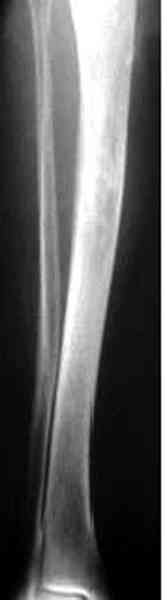

"При его рассмотрении с рентгенологом и морфологом сошлись, что это не фиброзная дисплазия, что было первым предположением по рентгенограммам. В полости было и мягкотканое образование. Окончательно заключение дадут через несколько дней"

По локализации и по характреру опухоли мало напоминает остеобластому, может, представленные биопсийные материалы адамантиномы помогут вашим морфологам дифференцировать опухоль (Basiloid cells, pseudoglandular pattern and peripheral palisading)

Недавно на нашей ежемесячной Morbidity&Mortality

conference мы разбирали похожий случай, ложный сустав большеберцовой кости после резекции опухоли.

К нашему онкологу-ортопеду обратился больной с жалобами на боли в голени, из рассказа - год назад была сделана биопсия большеберцовой кости, но название заболевания "не запомнил”.

Оперирован в военном госпитале с заменой сегмента

аллокостью большеберцовой кости и после демобилизации явился для постоянного наблюдения по месту жительства.

В литературе "A Classic Adamantinoma Arising from

Osteofibrous Displasialike Adamantinoma in the Lower Leg: A case report and Review of the Literature похожие снимки.

Наши имели проблему со сращением, пришлось им сделать динамизацию, дополнительную аутопластику.

Снимки представлены.